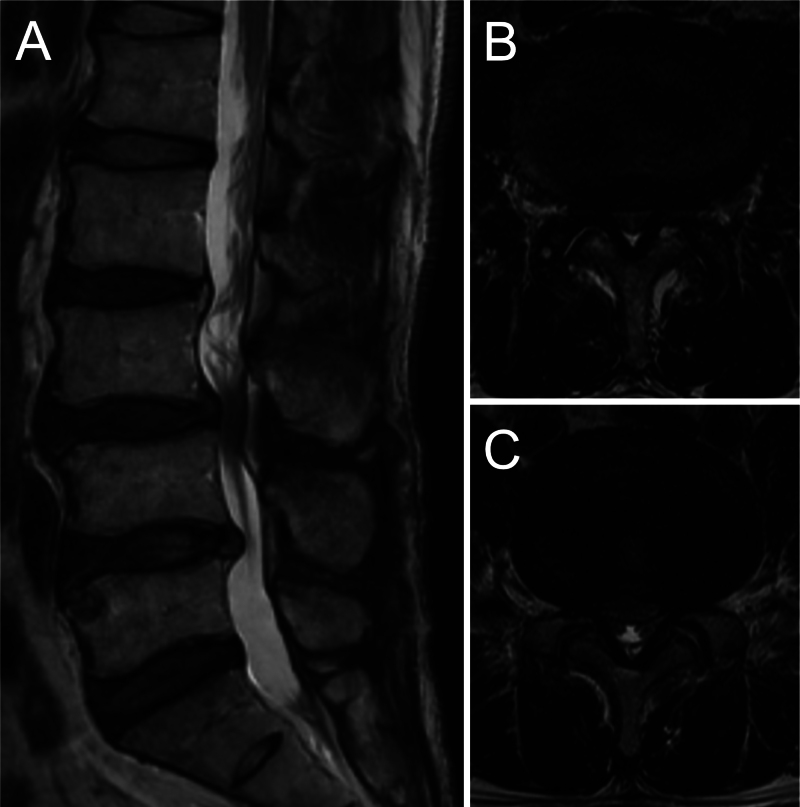

Observations: A 60-year-old man underwent UBE decompression for lumbar canal stenosis and experienced immediate symptom relief. However, 3 weeks postoperatively, he developed acute severe radicular pain, initially presumed to be caused by disc herniation. Despite repeated decompression, his symptoms progressively worsened. MRI findings remained nonspecific, without CSF leakage. Exploratory surgery ultimately revealed herniation of the cauda equina through an occult dural tear. Surgical repair led to rapid symptom relief and complete recovery without neurological deficits.

Abstract Image